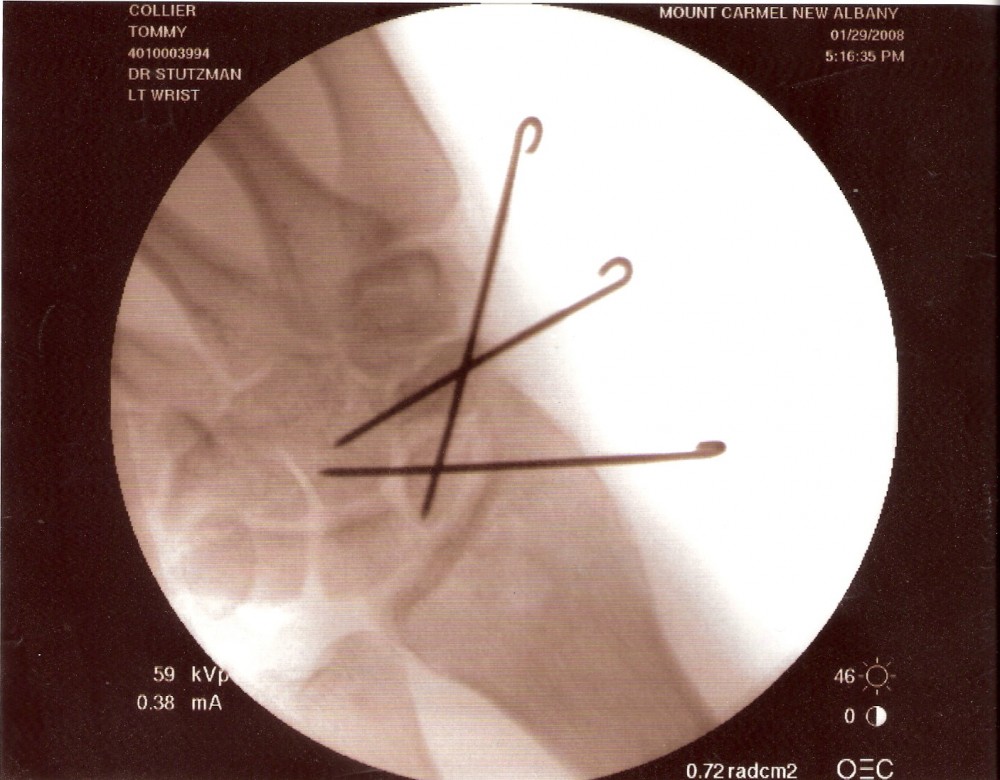

tommy collier: View Profile